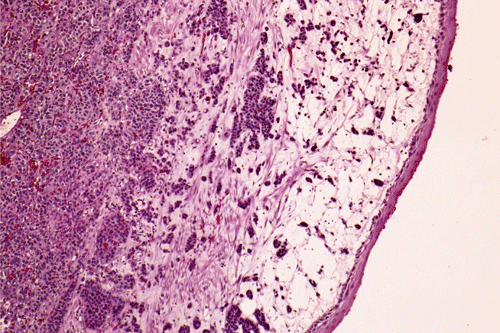

Clinical information: The patient was a 17 year-old boy who was in good health and was an active basket ball player. There was no history of asthma or other major illness. He developed chronic cough, wheezing and shortness of breath about 13 months before presentation.  The patient was initially treated in an outside facility under the clinical impression of asthma and his condition improved. Two months before presentation to our institution, he developed fever spikes with worsening of his cough and sputum production. There was also a weight loss of 10 pounds. His pulmonary function tests showed an obstructive pattern with both inspiratory and expiratory abnormal flow volume loops suggestive of variable intrathoracic airway obstruction. The PPD test was negative. A chest x-ray revealed mild atelectasis in the right upper lobe. A bronchoscopy was performed and a biopsy was taken. Based on the pathology results of the biopsy, a lobectomy of the right upper lobe was performed. The following photographs were taken from representative areas of the surgically resected specimen.

What is your histologic diagnosis?  Discussion